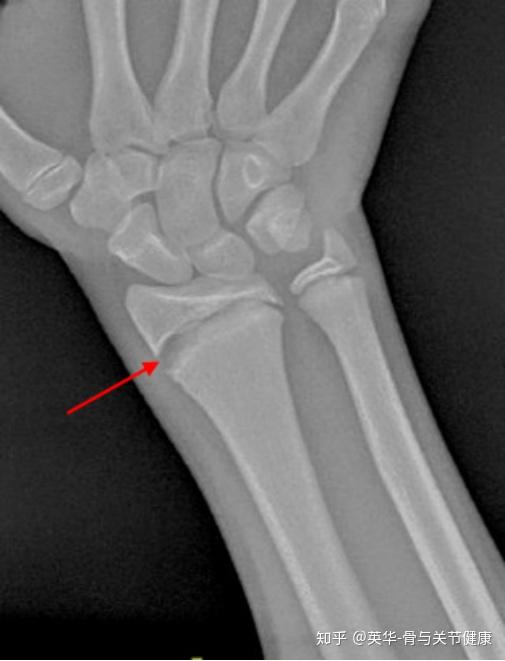

生长板骨折(损伤)Growth Plate (Physeal Fractures) 知乎 Radius Bone Growth Plate  Distal radius growth plate fracture what is a growth plate fracture of the distal radius? A distal radial epiphysis injury is a stress injury to the growth plate at the wrist end of the radius bone in the forearm. The metaphysis is the broad region of bone right next to the physis. The radius and the ulna are the two. Radius Bone Growth Plate.

Broken growth plate in wrist doctorvisit Radius Bone Growth Plate  These should be taken in at. All patients presenting with a suspected growth plate fracture require plain film radiographs (fig. The metaphysis is the broad region of bone right next to the physis. They are also common in the outer bone of the forearm (radius) and lower bones of the leg (tibia and fibula). The epiphysis is the name given. Radius Bone Growth Plate.

Wrist Fractures in Children Radius Bone Growth Plate  The metaphysis is the broad region of bone right next to the physis. The radius and the ulna. The physis is the growth plate, the part of the bone that has the cells that allows the bone to grow longer. The forearm is made up of two bones: The diaphysis is the narrow center part of the bone. A distal. Radius Bone Growth Plate.